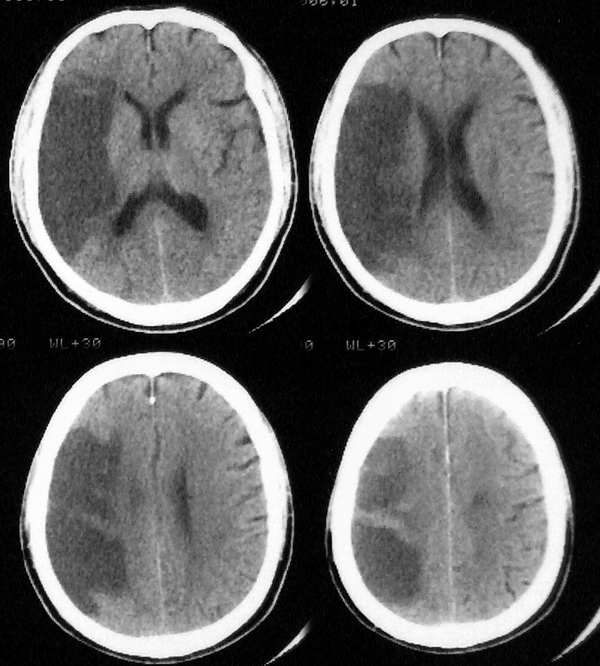

多由于脑部定位系统受到肿块压迫,引起感觉偏差所致。

特别要注意的是老年人爱咬腮帮,腔隙性脑梗塞常发生在有高血压、高血脂、糖尿病的老人身上,此病的早期症状中,就有爱咬腮帮的表现,容易被忽视。

原因是大脑局部的微血管发生梗死,脑组织缺血、坏死,使腮帮失去灵活运动能力。

如果发现老人常咬腮帮,或伴头痛、头晕、行走不稳、言语不清等症状,要赶紧就医。咬腮帮后,除了查找原因外,也要处理好被咬的伤口。

老年人“咬腮帮”也可能是脑梗塞引起的